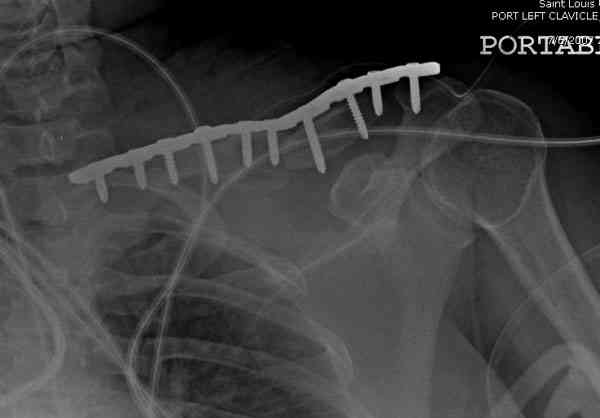

ГГШ> Результат стационарного лечения приведен на рентгенограмме (Xray_3).

Это картинка то есть через неделю после травмы, при выписке? Более чем приемлемо.

после изучения рентгенограмм могу сказать следующее:

1) после репозиции стало хуже

2) стояние фрагментов при выписке идентично таковому при пступлении - с выраженным смещением

Распределение мнений по перечисленным выше категориям приведено на гистограмме (см. Рисунок 1). Мнения разделись, и в аудитории преобладает убеждение, что сохранение смещения ключи.цы на величину диаметра без кортикального контакта между отломками и смещением до 3 см по длине у подростка 15 лет допустимо.

Оценка положения костных фрагментов должна осуществляться по рентгенограммам, вы.полненным в двух проекциях. Стандартная ( и почему.то считающейся достаточной в большинстве наших лечебных учреждений) передне.задняя проекция дополняется шейной проекций под уг.лом 45°. Смещения: расхождение в поперечном направлении, отсутствие кортикального контакта, укорочение ключицы более 1,5 см . недопустимы и должны быть устранены (11,12).

Рисунок 1 Распределение мнений травматологов по вопросу о допустимости сохранения смещения ключицы на величину диаметра без кортикального контакта между отломками и смещением до 3 см по длине (См. определение категорий в тексте)